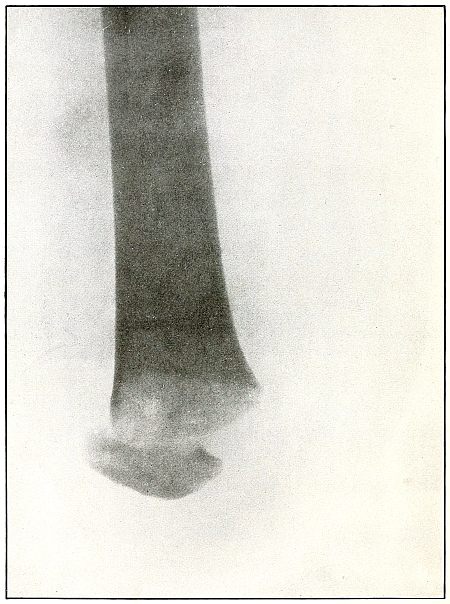

| 73. |

Gunshot wound, heel |

156 |

| 74. |

Gunshot wound, heel |

158 |